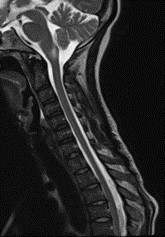

Una semana más reingresó a por servicio de urgencias debido a una exacerbación aguda del dolor abdominal previo y emesis. Se realizaron nuevos estudios de imagen complementarios: la colangiopancreatografía por resonancia magnética fue negativa, descartando enfermedades de la vesícula biliar y una nueva resonancia magnética contrastada del cerebro y la columna cérvico- descartó mielopatía en la columna vertebral, pero mostró un aumento considerable en la extensión del área de la lesión postrema con un notorio realce con gadolinio (Imagen 2). Se indicó un pulso de metilprednisolona de 1 gramo durante 3 días, se realizó una reinducción de ciclofosfamida; recibió un total de 2 dosis durante su hospitalización. Fue dada de alta nuevamente con mejoría clínica con una orden de continuar con ciclofosfamida, medicación previa y una orden para un perfil complementario de síndrome de antifosfolípidos y anticuerpos anti-acuaporina 4. En un control ambulatorio posterior, el paciente no refirió nuevas recaídas y mostró una IgM anticardiolipina positiva e IgM positiva para la glicoproteína beta 2 I con anticuerpos anti-acuaporina 4 negativos. Se añadió una dosis baja de inhibidores de la agregación plaquetaria y se realizó un diagnóstico altamente probable de SAF secundario a LES.

Imagen 2. A) RM del cerebro en corte sagital, en secuencia T2 donde se aprecia que la lesión hiperintensa persiste en el área postrema. B) RM del cerebro en corte axial en secuencia T1 posterior a administración de medio de contraste donde se observa un realce puntiforme en el área postrema.